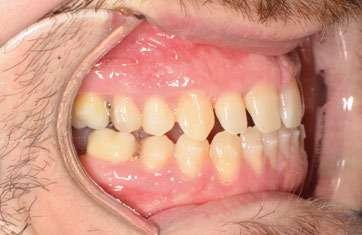

2. Análisis intraoral (Ilustración 2 y 3):

 Clase III molar y canina de Angle bilateral.

 Mordida abierta anterior > 3 mm.

 Compresión maxilar junto con mordida cruzada posterior bilateral.

 Línea media inferior desviada 2 mm hacia la derecha.

Ilustración 2. Fotografías intraorales iniciales de estudio.